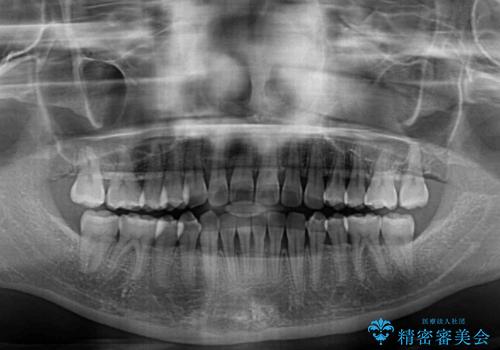

前歯の隙間と上下正中のズレを解消

正中がなかなか合わずに、2年近くの治療期間を要しました。